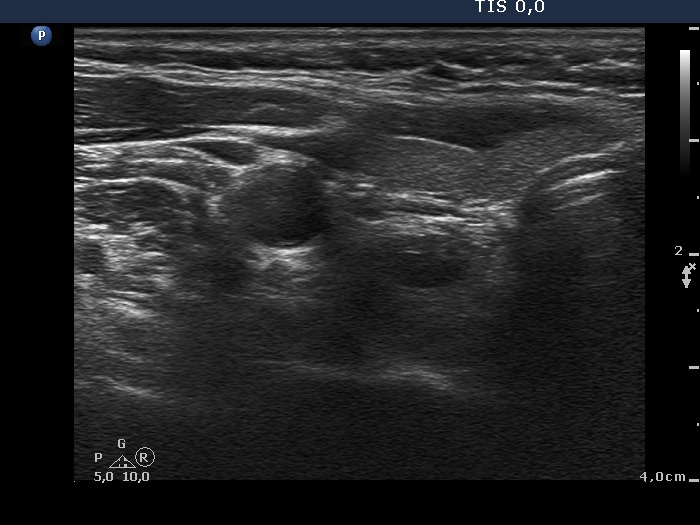

Clinical data: A 63-year-old woman was referred for exact localization of a parathyroid before surgery. The patient had diffuse complaints, including fatigue, depression, weight loss. On routine laboratory blood test, an elevated serum calcium level, thereafter an elevated parathormone level (154 pg/mL) were detected. MIBI scintigraphy disclosed parathyroid adenoma corresponding to the right lower parathyroid.

Ultrasonography. The thyroid was minimally hypoechoic and had several insignificant hypoechoic lesions. There was a solid-cystic mass dorsal to the lower pole of the right lobe.